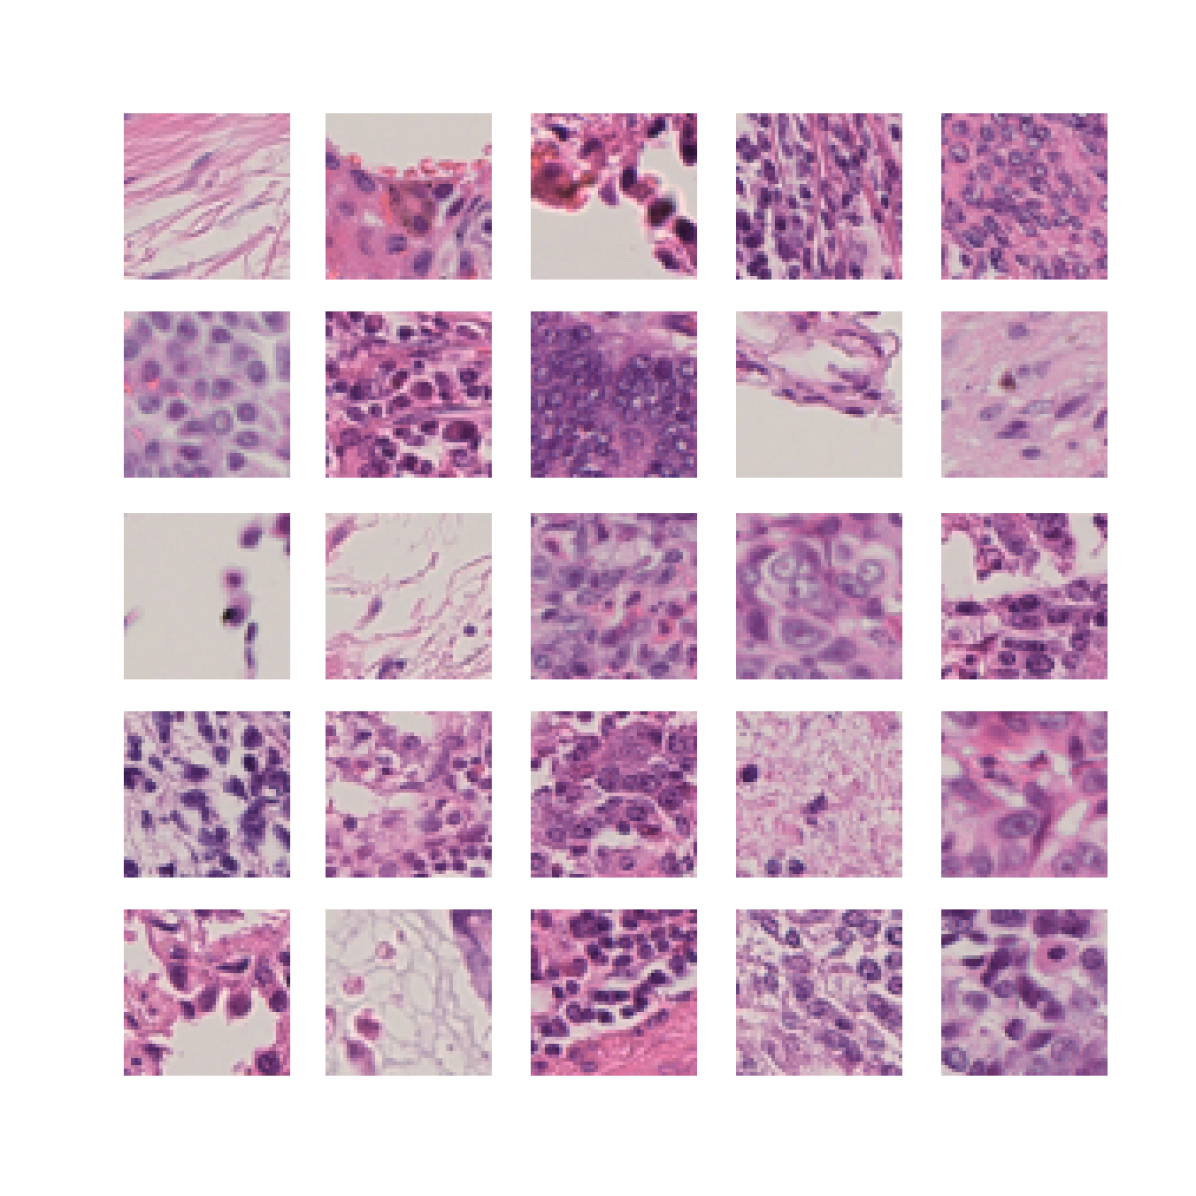

To further analyse the learned representations, we produce UMAP projections of the latent space labelled with the tissue types for the NCT tissue type classification task, as shown for CD3CD20 and SMA in Figure 4(a), and for all SegPath stains in Figures S8 and S9. These figures make the reasons for the varying performance of the privileged Siamese model more apparent. For stains with better performing privileged Siamese models, such as SMA, the UMAPs are very similar between Siamese methods and TriDeNT, with well-differentiated tissue type clusters. In those with worse performance, such as ERG, the tissue types are poorly differentiated, often with only adipose and background forming distinct clusters from the other classes. On closer inspection, it is notable in these projections that TriDeNT ♆ produces more well-defined and separated clusters in general than Siamese networks. This is further evidenced in Figure S7, where TriDeNT ♆ is shown to identify clusters with overexpression of a given gene significantly more effectively than an unprivileged Siamese model.

We also analyse the activation maps for each model using GradCAM as described in section S3. This offers more insight into the areas of the image which are contributing most heavily to the models’ representations. In Figure 4(b) we present some representative examples, however, a larger selection which was chosen at random is presented in Figures S10 to S25. The larger selection makes it easier to see the emergent patterns, including that privileged Siamese models tend to mainly identify features which are strongly present in both inputs, while unprivileged Siamese models tend to learn more diffuse features that are not specific to one cell phenotype or image region. TriDeNT ♆ incorporates both sets of features, learning both features specific to the privileged data and more the general features associated with unprivileged Siamese networks.